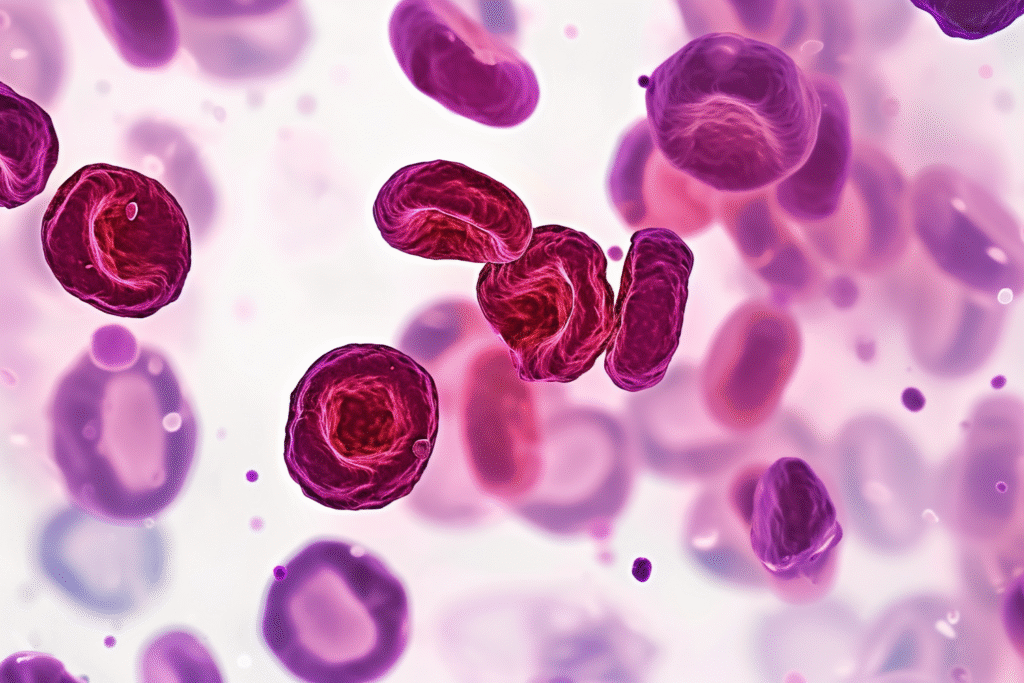

2. Blood levels of CtBP2 decline with age and are higher in long-lived individuals.

In their study, the scientists measured CtBP2 in many blood samples and found that levels consistently dropped with advancing age. Meanwhile, people from families known for exceptional longevity showed markedly higher CtBP2 concentrations compared with typical age-matched peers. Those with metabolic disorders or chronic disease had significantly lower levels.

That pattern suggests CtBP2 may serve both as a biomarker of aging and a mechanism by which healthy aging happens. It opens the possibility that by tracking CtBP2 you can estimate how “old” your body is biologically, not just chronologically.

3. Enhancing CtBP2 activity improved metabolic and physiological resilience in lab models.

In experimental models, activating CtBP2 resulted in improved glucose regulation, enhanced lipid metabolism and reduced signs of age-linked organ stress. When CtBP2 activity was lowered, metabolic dysfunction emerged more rapidly—mirroring patterns seen in medically frail aging humans. The lab data suggest CtBP2 isn’t purely passive—it may be a lever to improve health span.

For humans, this indicates a future where interventions target CtBP2 or its pathway rather than treat each disease separately. Instead of repairing damage after it appears, you might strengthen the system upstream, slowing the cascade of aging triggers before they take hold.